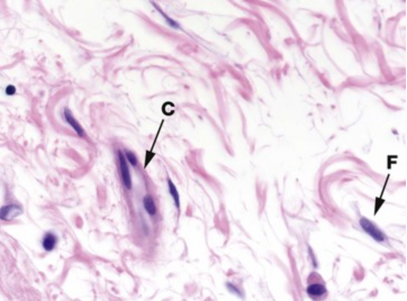

identify F and C, and what the image is of, with reasoning

A

areolar tissue of the submucosa of the bowel wall. the ground substance has not picked up any stain and appears white. few loose connective tissues in pink.

F is a fibroblast

C is a blood vessel

How well did you know this?